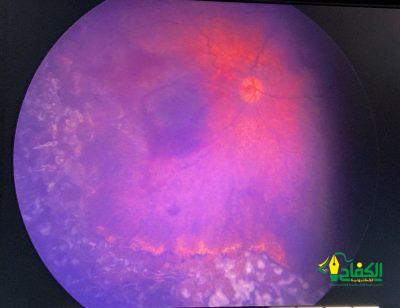

وبين التجمع الصحي أن الشبكية كانت متضررة في كلتا العينين وبالأخص العين اليمنى وأجريت عملية الليزر للعينين تحت التخدير العام بأسرع وقت ممكن وذلك بعد فحص المريضة من قبل فريق التخدير بقيادة استشاري التخدير الدكتور شادي بركات وتكللت العملية بالنجاح وخرجت الطفلة وهي بأتم الصحة والعافية دون مضاعفات تذكر أو الحاجة لأي رعاية حرجة ولله الحمد.